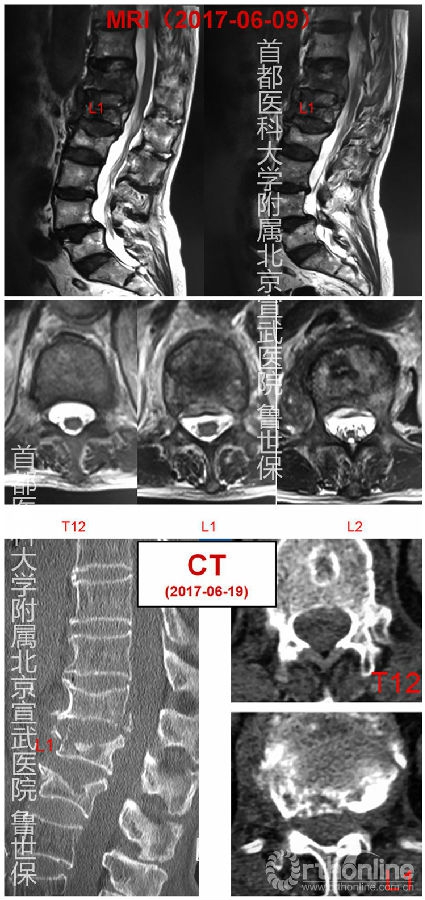

患者男,76岁,主因摔伤后腰背部疼痛4个月入院。

4个月前劳动后摔倒,出现腰背痛,程度剧烈,于卧床翻身及久坐后加重;无下肢无力、无感觉麻木,无间歇跛行。卧床3月,症状未缓解,为进一步治疗入院。病程期间无明显发热、盗汗、体重降低等。

入院完善资料

胸腰段后凸,翻身及下地活动时疼痛明显,胸腰段棘突轻度压痛及叩击痛。双下肢感觉、运动、反射未见明显异常;双侧直腿抬高(-);病理征(-)。T 36.7°;HR 74次/分;BP 140/80 mmHg。影像学检查示腰椎压缩骨折(L1、2)、腰椎滑脱(L4/5)。实验室检查示白细胞4.81*109、中性粒细胞3.51*109、淋巴细胞0.67*109、ESR46mm/h、CRP31.5mg/l、Hb131g/l。癌胚抗原9.55ng/ml。T-spot阳性。有阵发性房颤(140-180)、主动脉瓣重度返流、动脉瘤(髂总动脉)。入院后逐渐出现发热、低蛋白血症、贫血。

SPECT示胸12-腰2椎体及左侧第12肋局部骨代谢异常活跃,结合病史,考虑外伤后改变可能性大。随后行穿刺活检,穿刺出血性黄色胶冻样液体。病理(-),细菌培养(-),抗酸染色(-)。椎体穿刺液细胞学诊断镜下见红细胞,散在中性粒细胞及淋巴细胞。